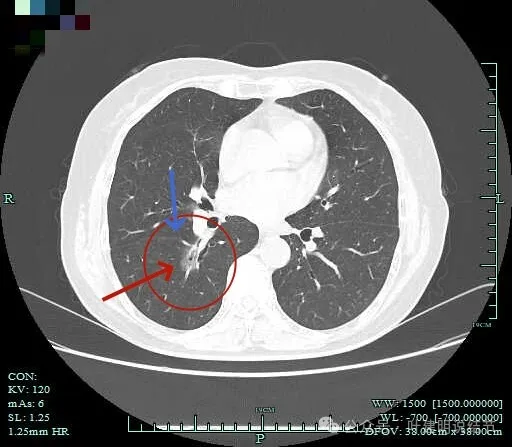

毛刺明显,轮廓清楚,灶内支气管扩张通气。

毛刺明显,灶内有实性成分出现。

毛刺征明显!!灶内密度杂乱。

靶重建显示混合密度,边缘毛糙,内部杂乱,灶内支气管通气且僵硬。

病灶影响到斜裂肺门部,边缘毛刺明显。灶内支气管僵硬。